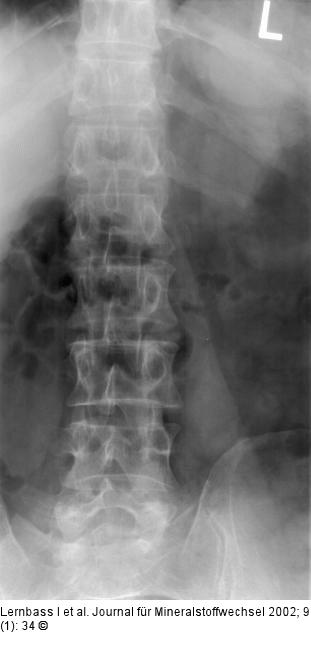

Abbildung 1: Skoliose Dezente skoliotische Fehlhaltung der LWS |